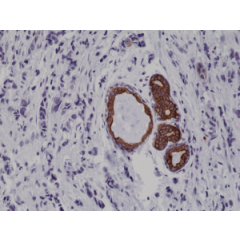

anti-Cytokeratin-7 (human), Rabbit Monoclonal (RM284)

anti-Cytokeratin-7 (human), Rabbit Monoclonal (RM284)

REV-31-1167-00 REV-31-1167-00-R100 100 µl CHF 468.00

anti-Cytokeratin-7 (human), Rabbit Monoclonal (RM416)

anti-Cytokeratin-7 (human), Rabbit Monoclonal (RM416)

REV-31-1302-00 REV-31-1302-00-R100 100 µl CHF 468.00